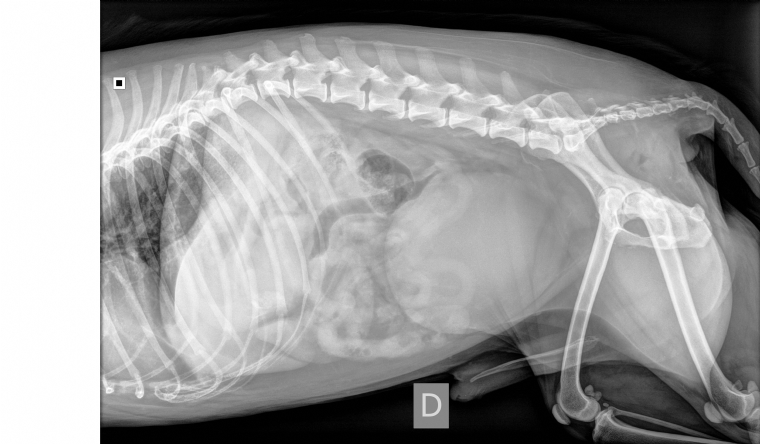

Mercredi 24 Août 2022 Animaux de compagniePhoto n° 1 : Radiographie abdominale de profil.

Un chien croisé terrier castré de 12 ans est présenté pour dysurie et ténesme depuis 15 jours.